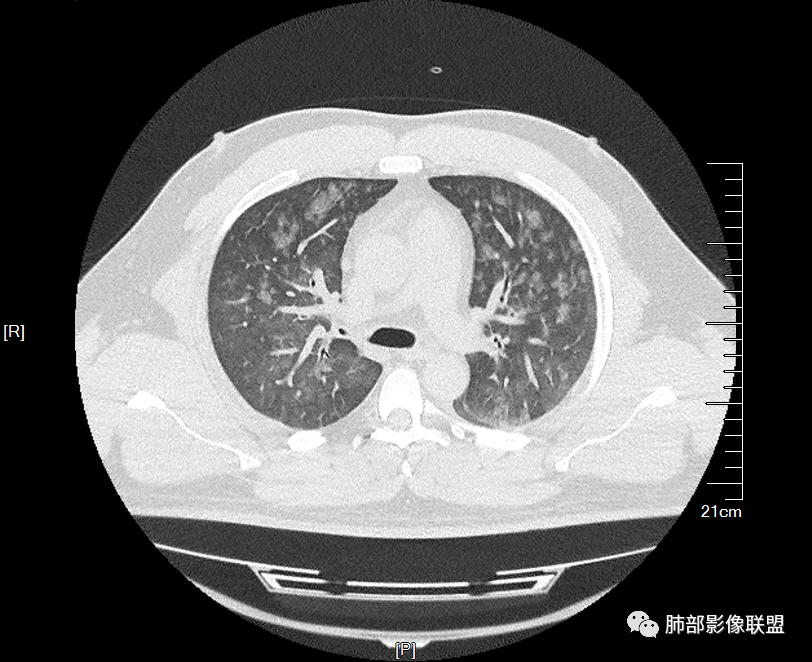

多发GGO结节,边界清,以全小叶、小叶中心为主:

小叶间隔增厚,无明显重力趋势

这里有一点重力趋势

中轴间质稍增厚

细网格也明显

中轴间质增厚,小叶间隔增厚,小叶内间质增厚,部分重力作用,双侧对称,胸水,按理淋巴道回流受阻有

肺水肿类病变有

问题是腺泡结节如何解释?

1.间质性肺水肿 :小叶间隔增厚,尚光滑,支气管血管束增粗,胸膜或叶间裂增厚,肺内有磨玻璃密度影,有重力分布趋势。

2.肺泡性肺水肿 :

(1)中央型分布:以肺门为中心,两肺中内带对称分布的大片状实变,称为“蝶翼征”。常见于心源性及肾源性肺水肿患者。也可表现为磨玻璃密度病灶,弥漫性分布或以小叶中心性分布。

(2)弥漫型肺水肿:弥漫分布于两肺内的多发斑片状磨玻璃密度及实变影,大小和密度不等,可融合成大片状阴影,可见空气支气管征。